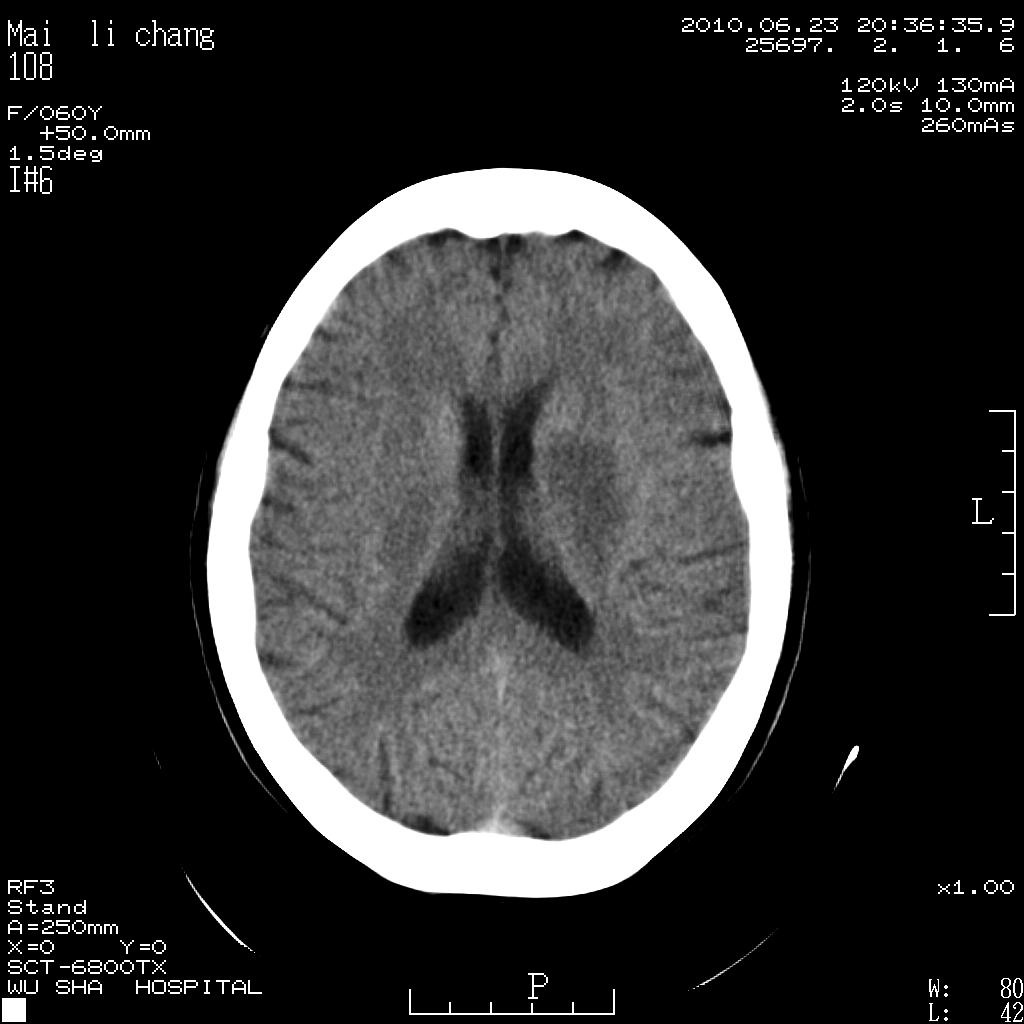

女性,60岁,右手无力一天

脑梗塞?并皮层下动脉硬化性脑病?还需要考虑什么?请大家指导,先谢了。

左侧基底节区及放射冠区多发脑梗塞。

左侧基底节区及侧脑室旁多发脑梗塞

2.左侧基底节区可见片状低密度病灶。

意见考虑脑梗塞。

左侧基底节区大面积梗塞,必要增强扫描协诊

左侧基底节及放射冠区脑梗塞。